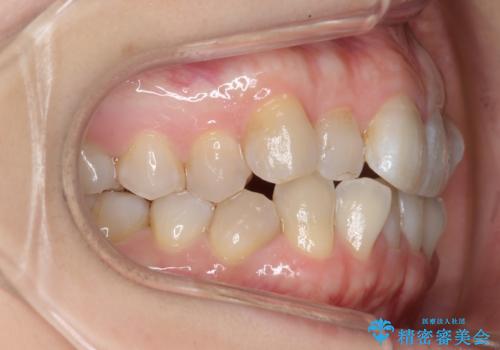

レントゲンを撮影したところ、右下4は神経のない歯で、外部吸収といって、根がだんだん短くなり、やがて抜けてしまう症状になっていました。また、アンキローシスを起こしている可能性があるため、動かない可能性が高い状態でした。

矯正治療で右下を抜歯し、スペースを天然の歯でつめる矯正治療を行いました。

治療期間はかかりましたが、右下4が一生もつとは思えない状態でしたので、人工物を入れないようにすることができました。